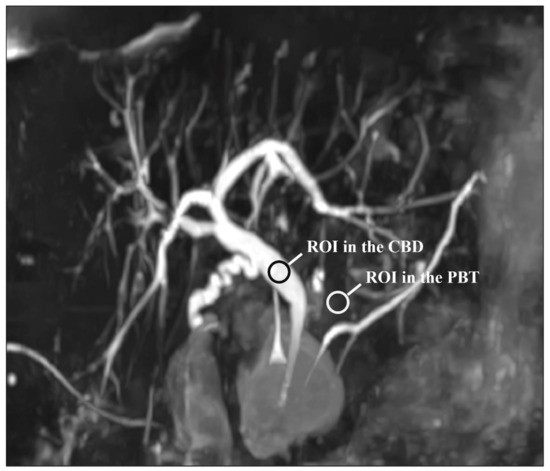

The readers also assessed the visualization of 12 segments of the pancreatic and bile ducts: the proximal and distal parts of the CBD; the confluence of the cystic duct and CBD; the proximal, central, and distal parts of the MPD; the intrahepatic bile ducts (IHBDs) to their primary branches (right and left IHBDs) and secondary branches (right anterior and posterior sectoral ducts and left medial and lateral branches). Each of these 12 segments were evaluated using a five-point Likert scale, with higher scores indicating better duct visualization (Table 2). Figure 2 shows these segments on an MIP reconstruction of a CS-BH-MRCP image.

Figure 2. The segments of the pancreatic and bile ducts on a MIP reconstruction image acquired with the CS-BH-MRCP sequence for qualitative image quality analysis. Numbers represent the main pancreatic duct (MPD) and bile ducts: (1) distal common bile duct (CBD), (2) proximal CBD, (3) cystic duct confluence, (4) left primary intrahepatic bile duct (IBD), (5) right posterior sectoral IBD, (6) right anterior sectoral IBD, (7) distal MPD, (8) central MPD, (9) proximal MPD. Left medial and left lateral ducts are not represented on this figure. Note that no right primary IBD duct was present in this patient.